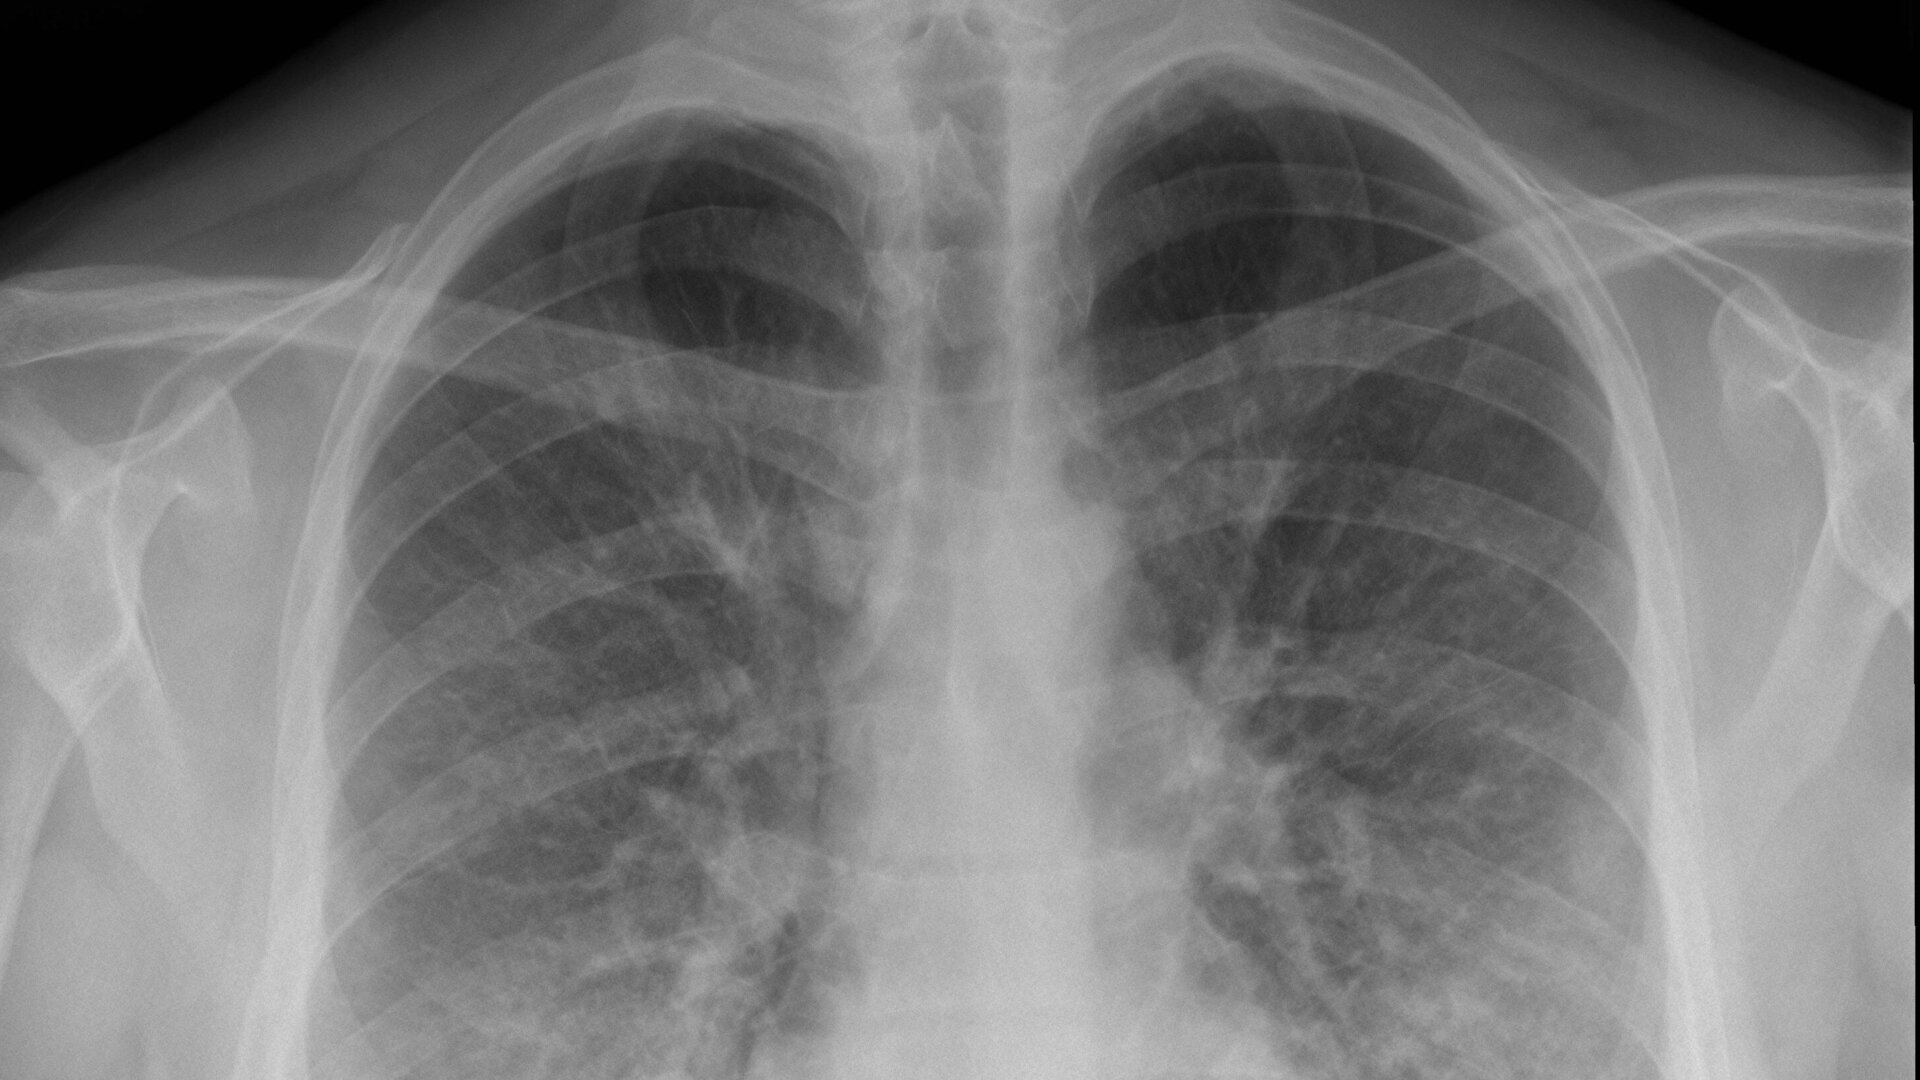

Sufferers of EVALI have experienced a range of severe respiratory and gastrointestinal symptoms, including trouble breathing and vomiting, with most people needing hospitalization. At this point, though, there is no concrete diagnostic test for EVALI. People have been diagnosed with it if they have a recent history of vaping and other potential causes for their symptoms such as infection have been ruled out. The median age of victims is 24, but the median age of those dead is 45.